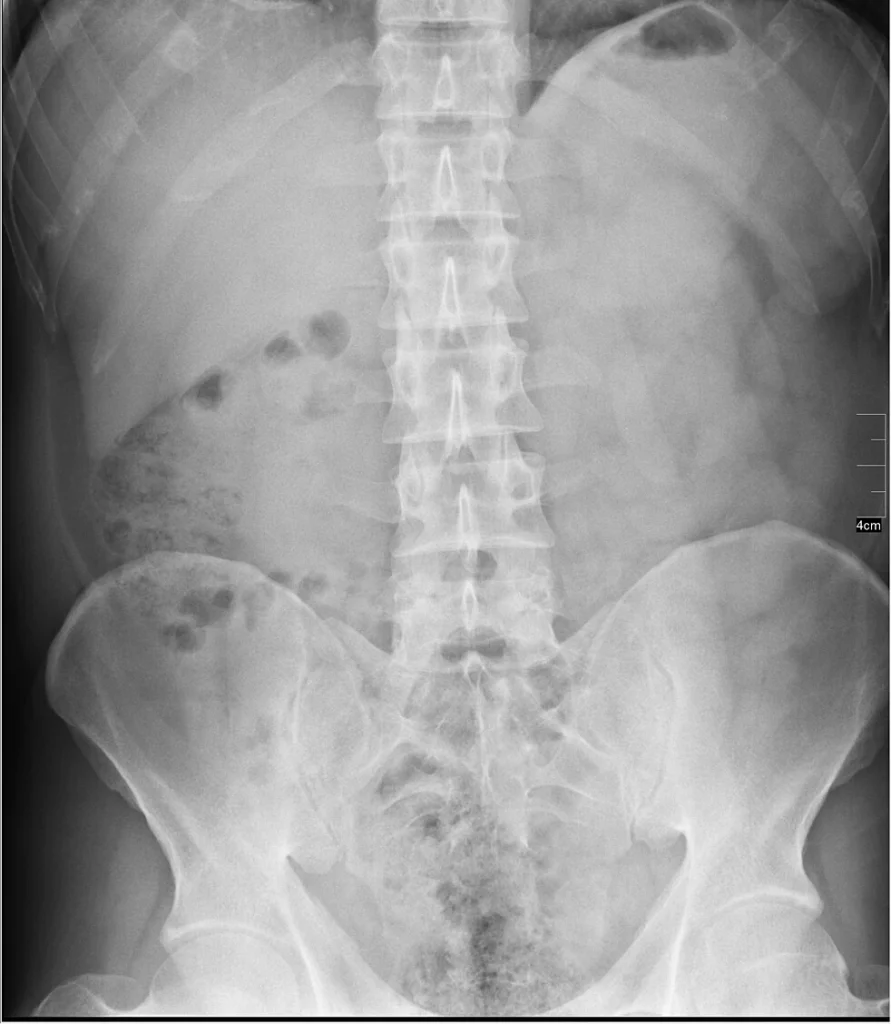

General X-rays are among the most commonly performed diagnostic imaging examinations. Using a controlled, focused burst of X-ray energy, images are captured of the specific area being examined to support accurate diagnosis. At YPS Imaging, we perform X-ray examinations for the chest, spine, bones, abdomen and various other parts of the body. Our qualified and experienced radiographers carefully position the area being scanned to ensure clear, precise images. X-ray imaging is non-invasive, quick and straightforward, making it a convenient option for patients and referring doctors.

Abdomen